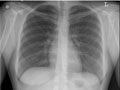

• Do a chest X-ray to look at your lungs.

CT scan.

This gives doctors a detailed picture of the lungs.